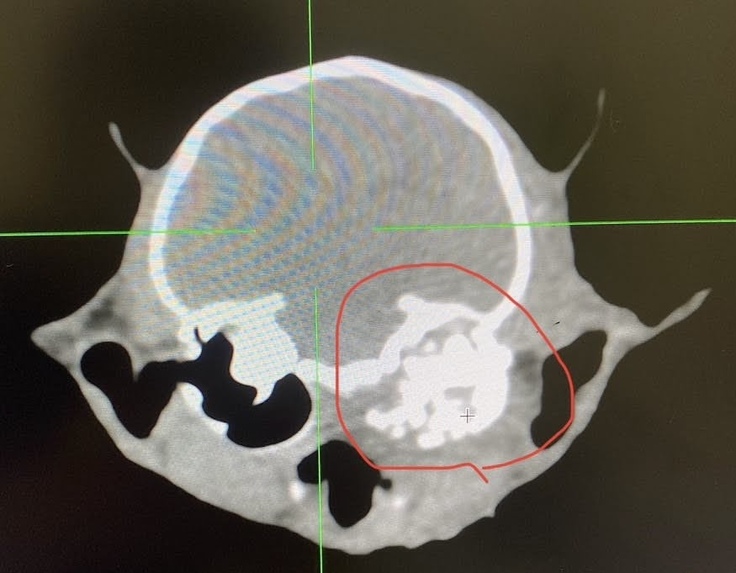

レントゲンでは頭蓋骨骨折と左の顔面も骨折していることが判明し、そのまま入院となりました。

さらにCT検査で詳しく調べたところ、左耳の付け根の骨は骨折で粉々になっており、平衡感覚や聴覚、視力、お顔を動かす神経などをも巻き込んでぐちゃぐちゃに壊れているような状態でした。